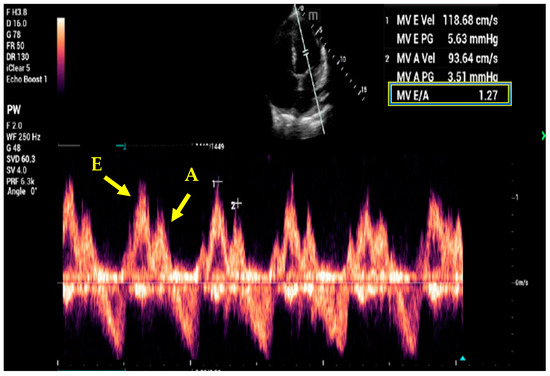

7. Basic and Advanced Echocardiography

- Kim, J.S.; Yang, J.W.; Yoo, J.S.; Choi, S.O.; Han, B.G. Association between E/e ratio and fluid overload in patients with predialysis chronic kidney disease. PLoS ONE 2017, 12, e0184764. [Google Scholar] [CrossRef] [PubMed]

- Nagueh, S.F.; Middleton, K.J.; Kopelen, H.A.; Zoghbi, W.A.; Quinones, M.A. Doppler tissue imaging: A noninvasive technique for evaluation of left ventricular relaxation and estimation of filling pressures. J. Am. Coll. Cardiol. 1997, 30, 1527–1533. [Google Scholar] [CrossRef]

- Nagueh, S.F.; Smiseth, O.A.; Appleton, C.P.; Byrd, B.F., 3rd; Dokainish, H.; Edvardsen, T.; Flachskampf, F.A.; Gillebert, T.C.; Klein, A.L.; Lancellotti, P.; et al. Recommendations for the Evaluation of Left Ventricular Diastolic Function by Echocardiography: An Update from the American Society of Echocardiography and the European Association of Cardiovascular Imaging. J. Am. Soc. Echocardiogr. 2016, 29, 277–314. [Google Scholar] [CrossRef]